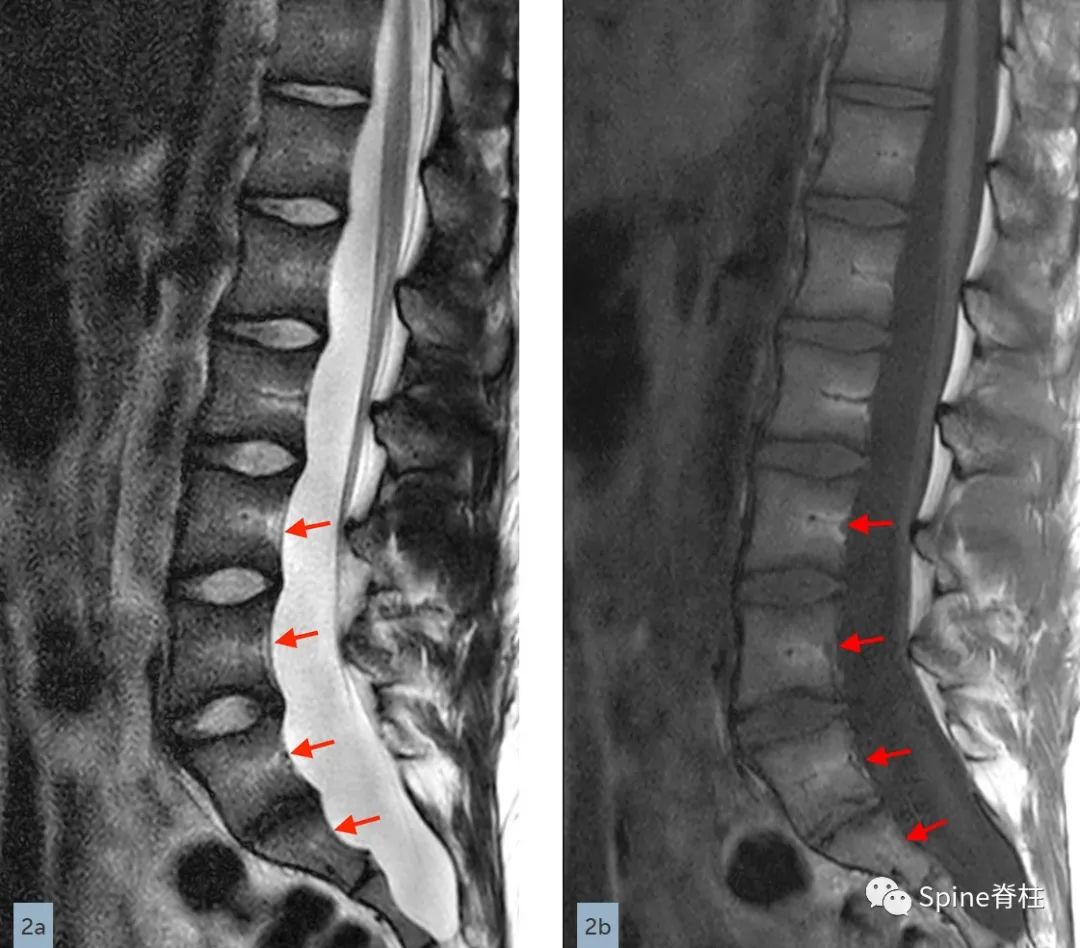

在矢状位T2(2a)和T1加权像(2b)上,多节段椎体后壁呈扇形缺损,缺少硬膜外脂肪(红色箭头),S1处的硬膜囊直径大于L4处。横断面T2(2c)和T1加权像(2d)提示硬膜囊膨胀,S1椎体后壁再次证实硬膜外脂肪缺失(红色箭头)。 其影像学表现符合硬膜扩张的诊断

矢状位T2(a)和T1(b)加权像提示下胸椎和上腰椎硬膜扩张伴显著的椎体后壁扇形凹陷(红色箭头)。轴位T2(c)和T1(d)加权像提示硬膜囊外侧膨出(绿色箭头)伴椎体扇形缺损。蓝色箭头是指继发于皮肤神经纤维瘤的多发性皮肤结节